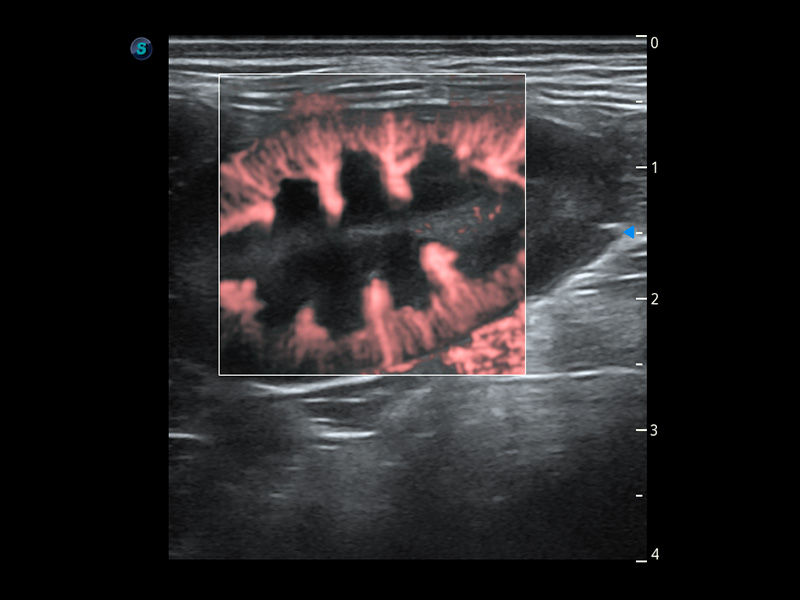

ProPet 60 作为一款高端台式动物超声设备,为动物医生的日常诊断提供了一系列贴合动物临床需求、解决临床实际问题的高级成像功能。凭借全系列高清探头,满足医生对腹部、心脏、生殖、浅表、肌骨等成像的所有需求,切实帮助您提升检查效率,提高诊断信心。

兽用彩色多普勒超声诊断系统

动物是人类最亲密的朋友和最值得信赖的伙伴。milan米兰也一直致力于探索动物专用的超声影像解决方案。 全新推出的ProPet系列,是milan米兰在动物超声影像智能化、专业化、精准化的一次跨越式革新。动物不能用言语来表述自己的不适,通过超声影像,ProPet系列搭建了动物医生与不同物种沟通的“桥梁”,为动物医生注入了“治愈之力”。